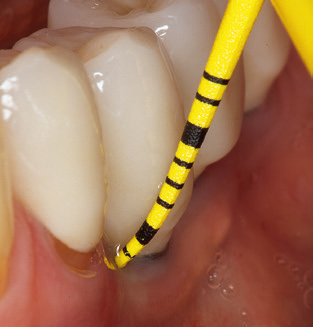

The current working concept for SPT

Updating the patient’s medical history is an important aspect of SPT and should occur at least once per year. It helps the dental team to identify and document any new risk factors. Especially when a patient is treated over many years, it is important to establish whether patient-specific and general health risk factors have changed. This primarily concerns a heightened risk as a result of diabetes, but other general conditions (cardiovascular disease and neoplasia) can also produce a modified risk profile as a result of the treatment performed and medication administered. Accordingly, updating the medical history as part of SPT is very important, as a modified risk profile may trigger the need to adapt the treatment interval. In the next step, it is important to afford the diagnostics due attention. Whilst instruments are a central aspect of SPT, findings and their documentation must never be neglected. The periodontological findings are essential for a good diagnosis; increases in the pocket depths and the BOP index are clear indicators of advancing periodontal and peri-implant disease. As such, the team should not shy away from probing implants too, with the aim of gathering the requisite data. At the same time, it is important to use periodontal probes with millimetre markings. Metallic probes have already been used for determining pocket depths around natural teeth for decades. In the case of implants, the challenge of recording correct and reproducible pockets depths is even greater. As the discrepancy between the implant diameter and the contour of the superstructure regularly results in overcontouring of the superstructure, flexible probes which still feature millimetre markings are a sensible solution for measuring pocket depths around implants (e.g., Colorvue Kit PCV11KIT6, Hu­Friedy; Fig. 4).

Fig. 4: Flexible probes with millimetre markings are recommended for the probing of dental implants (e.g. Colorvue Kit PCV11KIT6, Hu­Friedy). – Fig. 5a and b: A straight working tip (1P, W&H Dentalwerk Bürmoos GmbH) is a suitable instrument for use on all natural teeth. – Fig. 6: Curved working tips (3Pr/3Pl, W&H Dentalwerk Bürmoos GmbH) lend themselves to the processing of difficult-to-reach areas of the tooth and root surfaces (e.g. furcations). – Fig. 7: The tapered, hexagonal implant cleaning tip (1I, W&H Dentalwerk Bürmoos GmbH) permits atraumatic and efficient cleaning of the crown and abutment surfaces. – Fig. 8: Titanium and carbon curettes are suitable instruments for the manual cleaning of the implant surfaces.